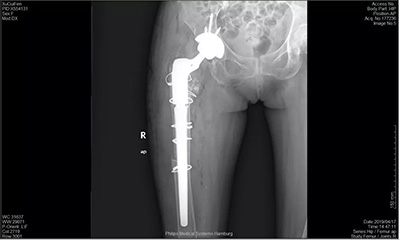

2、髖關(guān)節(jié)翻修術(shù)

人工髖關(guān)節(jié)的平均壽命在15至20年左右,有于假體使用時(shí)間的延長(zhǎng),假體的磨損,將會(huì)出現(xiàn)關(guān)節(jié)松動(dòng)、下沉、磨損及假體周圍骨溶解等問(wèn)題,從而導(dǎo)致患者關(guān)節(jié)再次出現(xiàn)疼痛。如果人工關(guān)節(jié)松動(dòng)、脫位、髖臼磨損等問(wèn)題導(dǎo)致關(guān)節(jié)疼痛影響生活,可以通過(guò)人工髖關(guān)節(jié)翻修手術(shù)解決病人痛苦,提高生活質(zhì)量。

3、3D打印應(yīng)用于復(fù)雜髖關(guān)節(jié)置換

科室運(yùn)用3D打印技術(shù)輔助術(shù)前打印患者髖關(guān)節(jié)髖臼側(cè)模型,全面細(xì)致地了解擬行手術(shù)側(cè)髖臼的骨量與骨質(zhì),完成各種解剖學(xué)測(cè)量,為精確手術(shù)方案提供依據(jù),降低手術(shù)風(fēng)險(xiǎn)。為個(gè)性化的手術(shù)治療提供模擬輔助,擇優(yōu)選擇手術(shù)器械,預(yù)設(shè)手術(shù)入路,縮短手術(shù)時(shí)間,減少創(chuàng)傷,規(guī)避手術(shù)中可能的風(fēng)險(xiǎn);3D打印技術(shù)充分突出其精準(zhǔn)、快速的優(yōu)勢(shì),為我科在臨床的診治提供一種全新的模式。